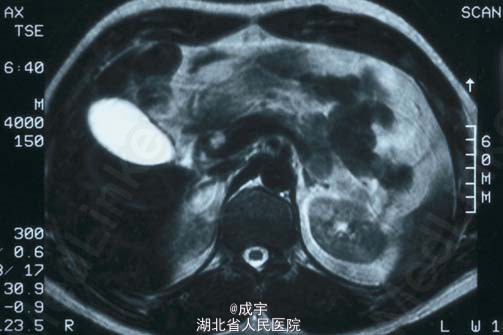

体检:病人呈Cushing’s 综合征表现,满月脸、皮肤毛细血管扩张、皮肤萎缩、水牛背、腹及上肢紫纹、远端肌肉萎缩和外周水肿。血压:158/90mmHg。 辅助检查:检查显示高胆固醇血症、空腹血糖增高、糖化血红蛋白5.2%、低钾,无其它电解质紊乱,无肾功不全。 连续2天尿游离皮质醇明显增高,晨血ACTH和皮质醇明显增高,无ACTH/皮质醇正常昼夜节律,无论是高还是低剂量的地塞米松都不能抑制血和尿中的皮质醇,尿中的5羟吲哚乙酸正常。垂体MRI检查未发现异常,双侧岩下窦标本也未显示中央-外周的ACTH梯度。 CRH刺激试验证实存在异位ACTH存在,胸片、支气管镜及灌洗液细胞学检查无阳性发现,肺CT显示左上肺下舌叶有一12mm的小结节(见图2),腹部CT显示肾上腺及其它腹部器官无异常。